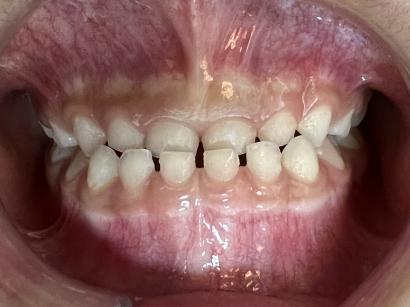

你见过这样的牙齿吗?这些就是典型的地包天。

地包天又称前牙反颌。是在乳牙期、混合牙期和恒牙期非常容易发生的一种牙齿畸形。正常的情况下,上颌的牙齿盖住下颌的牙齿。地包天反过来,下颌牙齿往前伸,下颌牙齿盖住上颌牙齿。

治疗前